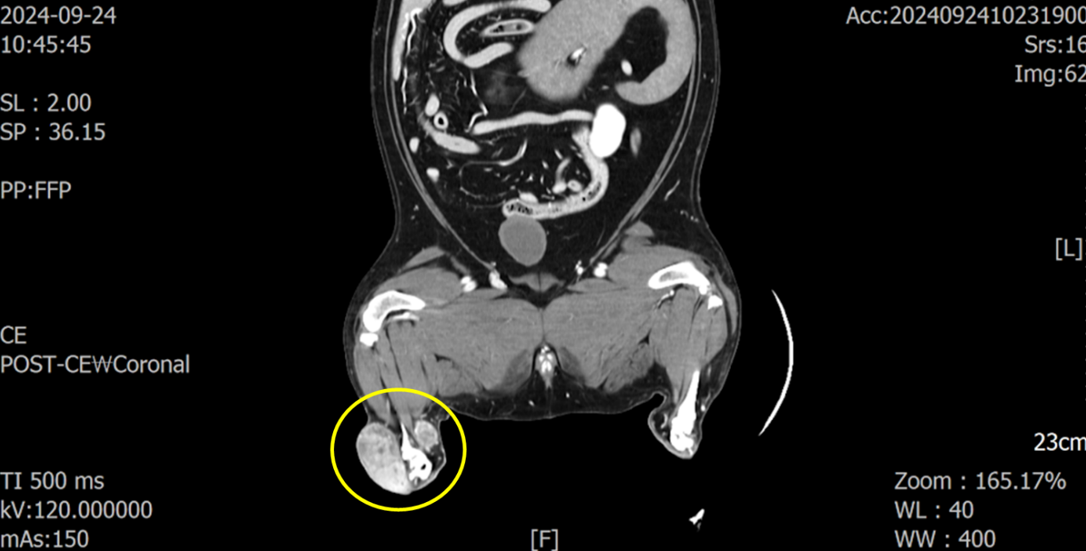

CT 촬영을 통해 해당 종양이 아킬레스건 주변을 둘러싸고 근육 침습도 일으키고 있는 양상을 확인하였습니다.